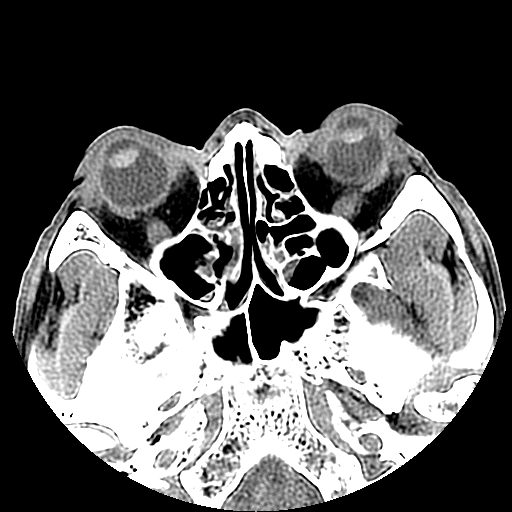

以下是引用liaoqiang在2008-7-16 21:15:00的发言:[br]右侧鼻骨骨折

以下是引用zxd95在2008-7-16 21:39:00的发言:[br]右侧上颌骨额突骨折。[br][br][br][br]